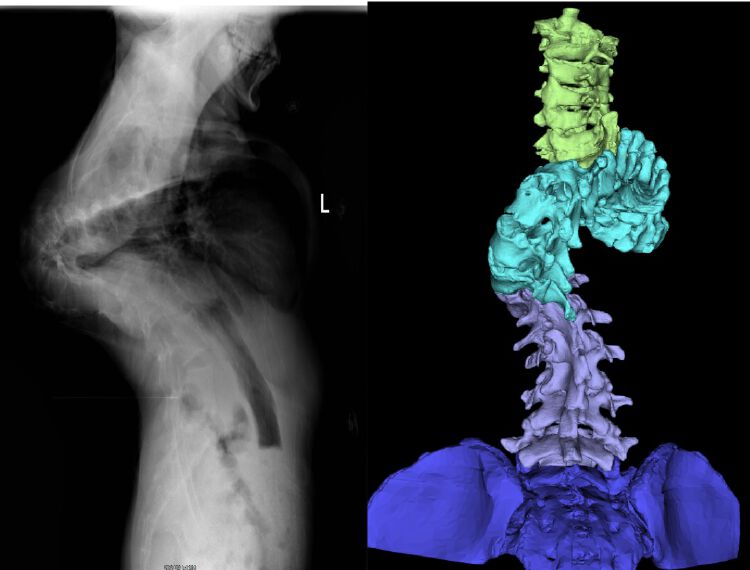

小那的脊柱畸形角度大,脊柱几乎拧成麻花。

经王庆贺医生诊断,小那确诊为重度先天性脊柱侧凸和后凸畸形,侧凸角度达到135度、后凸角度达到138度,一半以上的胸椎椎体有超过90度的严重旋转。简单地说,他的脊柱已经拧成了几乎对折的麻花,由于胸腔和腹腔的容积也显著减小,心肺、胃肠等内脏受到严重压迫,导致出现呼吸、消化、循环等功能障碍,他不能做大的运动,也不能正常饮食,甚至可能出现像消化道出血这类严重的并发症。小那的身高只有131cm,体重仅32公斤。

经过4个月的牵引治疗,小那的脊柱畸形获得了显著的改善:后凸角度从138度减少到70度,侧凸角度从135度减少到51度。